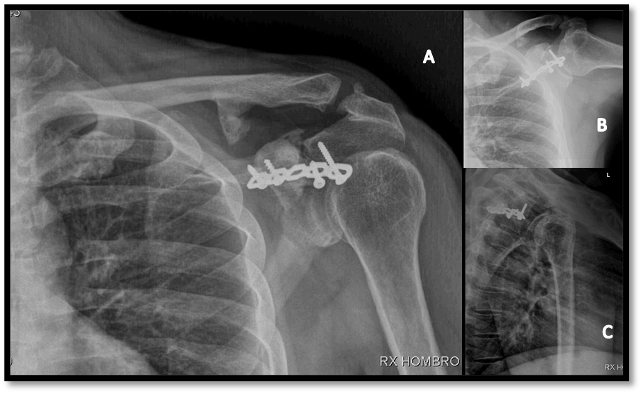

En las radiografías de control postquirúrgicas inmediatas se evidencia adecuada reducción con congruencia articular. Tras cinco semanas después del accidente, se proceden a retirar las clavijas, fig (3).

El paciente inició terapia física y se le retiró el cabestrillo. Insistiendo en el restablecimiento de la movilidad activa del hombro y el fortalecimiento muscular periescapular, rotadores y abductores. En el seguimiento clínico a los tres meses, mostró una rehabilitación satisfactoria logrando adecuado rango de movimiento, conservando una proporcionada fuerza muscular (fig. 4).

Las radiografías al año muestran signos de consolidación ósea, congruencia articular acromiocavicular (Fig. 5), en la valoración funcional del hombro el paciente presenta los rangos de movilidad articulares completos (Fig. 6).